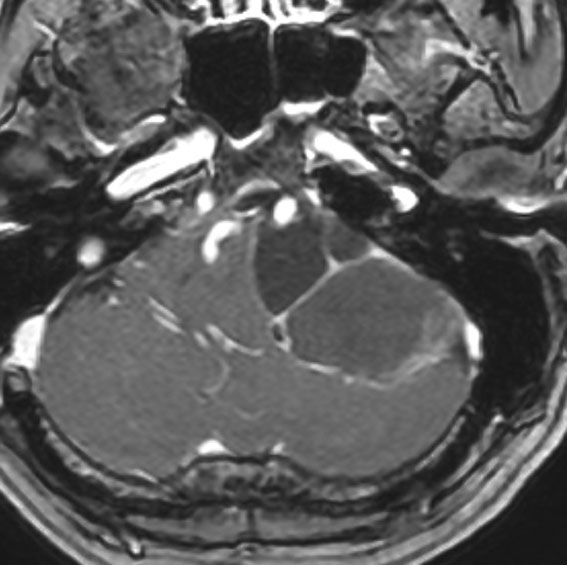

腫瘍が嚢胞性拡大で大きくなって,腫瘍内出血して,閉塞性水頭症になって意識障害を生じた患者さんです。このような事態になると臨時手術で腫瘍を摘出します。

大きなのう胞性聴神経腫瘍です。いくつかの袋が重なって腫瘍を形成しています。橋や延髄(脳幹部)が変形して,第4脳室がつぶれて閉塞しています。袋の周りが白く線状に造影されているのですが,この袋の壁だけに腫瘍細胞がありますから,これを剥がすように摘出します。顔面神経が薄くなって袋の壁にくっついているのですが,袋を破ってくしゃくしゃにすると顔面神経の位置が変わってしまって,顔面神経を損傷することがあるので要注意です。のう胞性聴神経腫瘍の方が顔面神経麻痺の後遺症の頻度が高いという報告もあるくらいです。この患者さんは迷走神経と舌咽神経の圧迫も強くて,ご飯を飲み込むことが難しくなっていました(嚥下障害)。

また,この患者さんは急に容態が悪くなって意識障害となりました。何故なら腫瘍の内部で出血したからです(黄色の矢印の部分)。第4脳室が詰まって閉塞性水頭症になって側脳室が拡大しています(右の画像)。